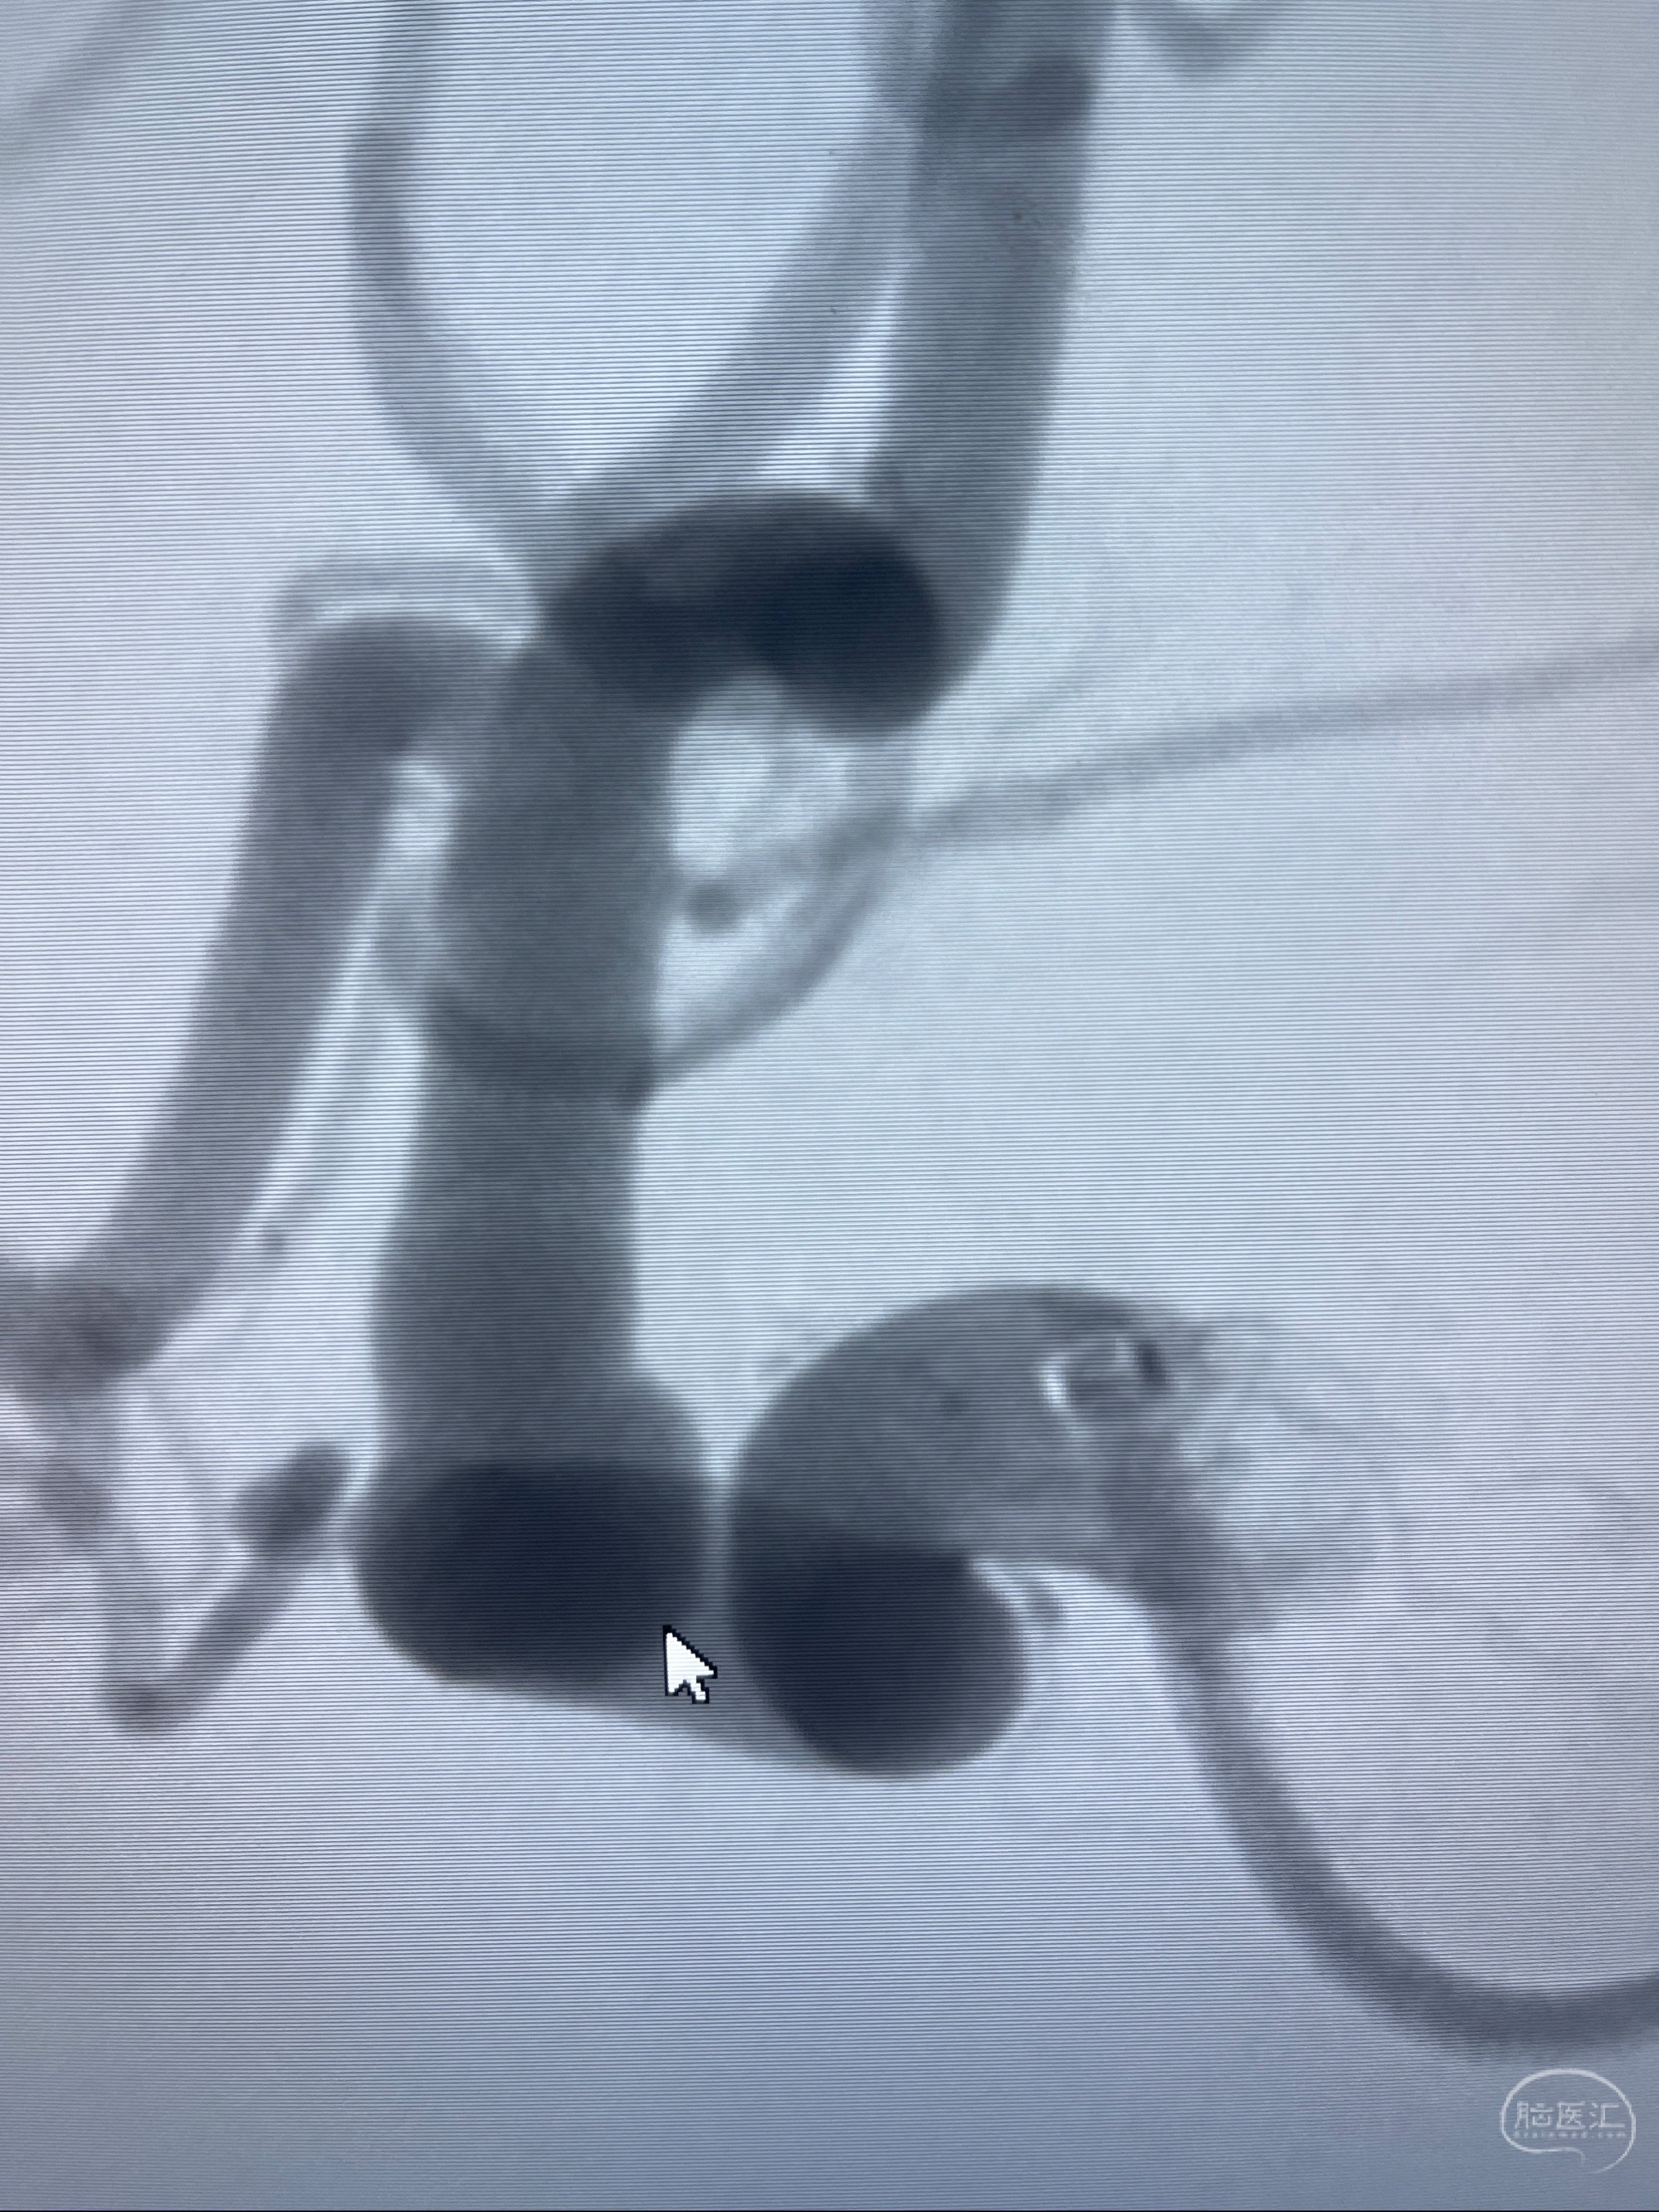

1.右侧颈内动脉眼动脉段动脉瘤

CTA示:右侧颈内动脉C6段见指向下方的突起,余左侧颈内动脉、双侧椎动脉、大脑前动脉、大脑中动脉、大脑后动脉及基底动脉走形正常,未见明显扩张及狭窄,局部未见明显瘤样扩张。

2023-07-27全脑血管造影:双侧颈内动脉眼动脉段动脉瘤,右侧较大

2023-08-01全麻下行双侧颈眼动脉瘤支架辅助栓塞

- pipeling4.5-20mm

- pipeline 4.0-20mm